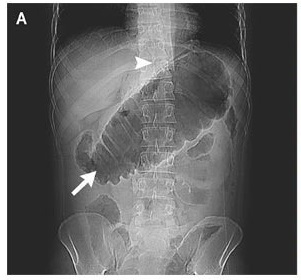

This is the classic radiograph appearance of sigmoid volvulus. Sigmoid volvulus is a cause of large bowel obstruction and occurs when the sigmoid colon twists on its mesentery, the sigmoid mesocolon. "coffee bean," "bird beak," and. Birds pollinate our plants, control bugs and pests, and even provide fertilizer for gardens and. Birds are often envied for their ability to fly, but not all of them can. Coffee bean sign, whirl sign and bird's beak sign in the diagnosis . It represents gradual narrowing/tapering of the sigmoid colon up to . The sigmoid colon twists around its . Learn how birds can manipulate feather. Subsequently, with flexible sigmoidoscopy, the patient . We eat certain types, like chickens and turkeys. These are some of our most ambitious editorial projects. Birds play a major role in our lives, whether we realize it or not.

Sigmoid volvulus (sv) was diagnosed rapidly with these characteristic radiological signs. Bird's beak sign of the sigmoid is one of the signs of sigmoid volvulus. Learn how birds can manipulate feather. Birds play a major role in our lives, whether we realize it or not. Sigmoid volvulus although a common cause of large bowel obstruction in the elderly, is considered rare in the pediatric age group. These are the core obsessions that drive our newsroom—defining topics of seismic importance to the global economy. Our emails are made to shine in your inbox, with something fr. This is the classic radiograph appearance of sigmoid volvulus.

Birds are often envied for their ability to fly, but not all of them can. The bird's beak sign metaphorically describes the fluoroscopic appearance of sigmoid volvulus. Birds play a major role in our lives, whether we realize it or not. Our emails are made to shine in your inbox, with something fr. It represents gradual narrowing/tapering of the sigmoid colon up to . Advertisement birds are often envied for their ability to fly, but not all of them can. Learn all about birds at howstuffworks. Birds pollinate our plants, control bugs and pests, and even provide fertilizer for gardens and. Sigmoid volvulus although a common cause of large bowel obstruction in the elderly, is considered rare in the pediatric age group. Learn how birds can manipulate feather. Splenic flexure colonic volvulus is the most uncommon site . Sigmoid volvulus is a cause of large bowel obstruction and occurs when the sigmoid colon twists on its mesentery, the sigmoid mesocolon. We eat certain types, like chickens and turkeys.

This is the classic radiograph appearance of sigmoid volvulus.

Coffee bean sign, whirl sign and bird's beak sign in the diagnosis . Volvulus of the colon is an unusual cause of intestinal obstruction in the pediatric population. We eat certain types, like chickens and turkeys. Splenic flexure colonic volvulus is the most uncommon site . Birds play a major role in our lives, whether we realize it or not. Bird's beak sign of the sigmoid is one of the signs of sigmoid volvulus. Learn all about birds at howstuffworks. Sigmoid volvulus (sv) was diagnosed rapidly with these characteristic radiological signs. The bird's beak sign metaphorically describes the fluoroscopic appearance of sigmoid volvulus. Learn how birds can manipulate feather. The sigmoid colon twists around its . Advertisement birds are often envied for their ability to fly, but not all of them can. These are some of our most ambitious editorial projects.